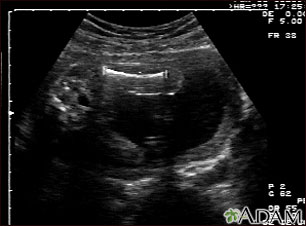

This is a normal ultrasound of the fetus performed at 19 weeks gestation. A clear view of the left femur (the large bone of the leg) can be seen in the middle, towards the top of the ultrasound screen.